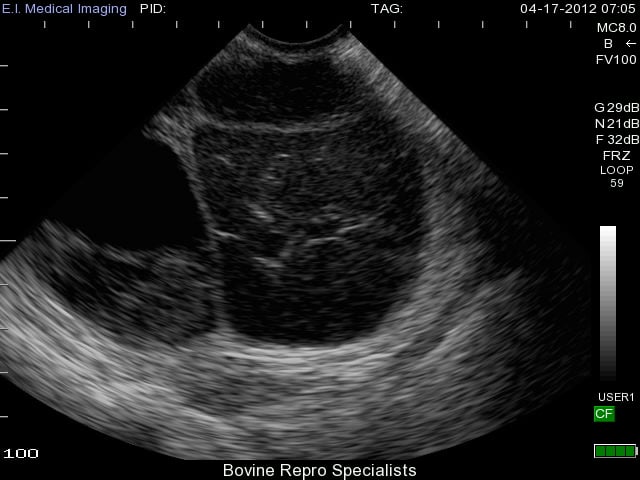

Development of follicular cysts in cows occurs when a follicle reaches the ovulatory size (about 17 to 19 mm), but fails to ovulate leaving a large persistent follicular structure on the ovary. A single follicular cyst or multiple cysts can form on the ovary (s). Length of time for the anovular follicle to persist on the ovary before it’s considered a follicular cyst is usually at least 10 days. There are various classifications of a “true follicular cyst”, but a classic identifying feature is a follicular structure on the ovary that is at least 25 mm in size in the absence of any corpus luteum. The appearance of follicular cysts is clear using ultrasound with the large cystic structure having a very thin outer wall with black fluid extending to its outer edges as shown in the image below.

As you can see, diagnosis of this type of cyst is clear with use of an ultrasound, and the presence of a second follicular cyst is evident on the left side of the ovary as well. Rupture of these cysts is quite easy from rectal palpation, which can traumatize the ovary leading to hemorrhaging, and possible adhesion formation on the ovary. The less invasive approach of using an ultrasound can reduce the chances of rupturing follicular cysts, and also is extremely effective to determine whether the cyst is active or benign. Palpating any other structure on an ovary is extremely difficult when a cyst is present, so many times an active corpus luteum is not found on the ovary along with the cyst. An example of this is shown below where the cyst is very prominent on the left side of the ovary, but can be classified as benign due to the corpus luteum sitting to the right of it.